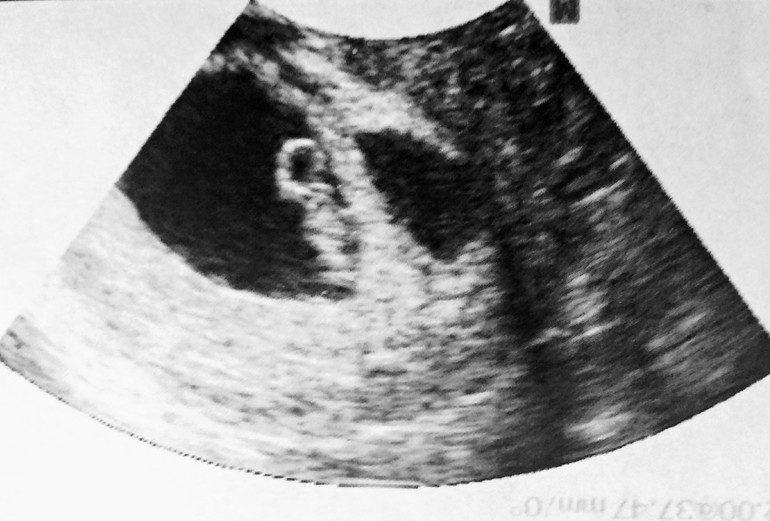

СамочувствиеВчера снова увиделись с крохой. Деть почти 2 см, моторчик работает 170 уд/мин. Врач сказал, что матка в тонусе, но я думаю, что тонус был только на приеме у врача, в кабинете было холодно, мне страшно +усталость и тошнота, я чувствовала как у меня все внутри прям скручивается.

Моя такая в 7,5 была